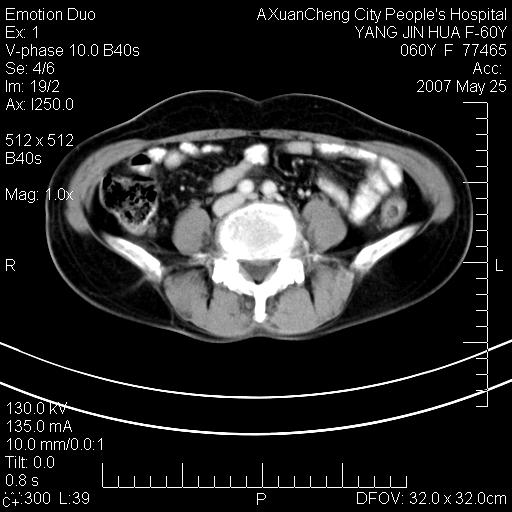

发现左侧腰背部包块40余年,逐渐长大,质软,局部表面可见扩张的血管影

左背部皮下良性肿瘤,密度不均,边界不清,内有脂肪、钙化,增强扫描无明显强化,血管平滑肌脂肪瘤?进一步诊断有困难,建议穿刺活检。

左侧背部皮下混杂密度肿块,结构较疏松,边缘欠光整,内有多发斑点状钙化,考虑:皮下血管瘤。

这个病理增强扫描之前,我们是考虑是血管瘤,可是现在增强后一点强化都没有,还能考虑是血管瘤吗

其内可见斑点状静脉石,血管瘤有时就不增强化,还是血管瘤。

1、病灶内有小点状钙化,静脉石?这可是血管瘤诊断的重要征象

2、病灶内有脂肪组织增生,血管瘤有此特点